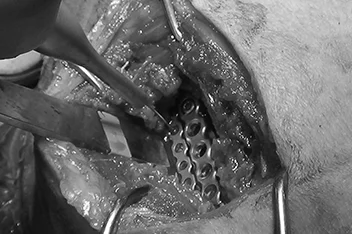

• 복합골절

• 최소침습 골절수술